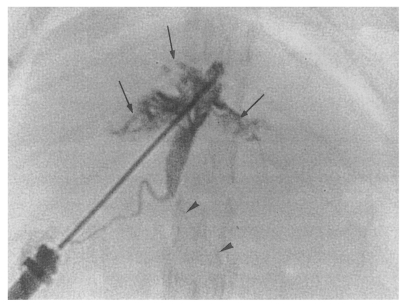

Cholangiographic findings

Cholangiography could not be performed in the normal control group because the bile ducts were too fine to puncture with a 26-gauge needle (Fig. 1). Cholangiograms showed moderate or marked dilatation of the bile duct confluence and of the proximal extrahepatic bile duct in the primary infection control group, the secondary infection control group, the reinfection I group, the reinfection II group, and the infection following immunization group. By contrast, the distal extrahepatic bile duct had a normal or near normal caliber (Fig. 8). In the primary and secondary infection control groups, and the infection following immunization group, multiple irregular filling defects were demonstrated on cholangiograms, indicating worms or desquamated materials (Fig. 9). These filling defects were hardly seen in the reinfection I and II groups. In these groups, the degree of dilatation of the bile duct at 26 weeks after reinfection (33 or 28 weeks after treatment, respectively) was slightly milder than that at 6 weeks after reinfection (13 or 8 weeks after treatment, respectively).

Cholangiograms showed moderate or marked dilatation of the bile duct confluence and of the proximal extrahepatic bile duct in rats with active or a previous infection, whereas the distal extrahepatic bile duct had a near normal caliber. In rats with active infection, worms or desquamated materials showing multiple irregular filling defects were demonstrated. As was the case for sonography, filling defects were hardly noted on cholangiograms in the reinfection groups. The finding of moderate or marked dilatation of the proximal extrahepatic bile duct persisted after C. sinensis treatment. This cholangiographic feature showed fusiform dilatation of the extrahepatic bile duct resembling that of a choledochal cyst, Todani's classification 1C (Todani et al., 1977). All of the cholangiograms demonstrated the long common channels of the bile duct and pancreatic duct. Such an anatomical change may have influenced the niche afforded by the bile ducts. Some pathophysiologic changes such as stagnated bile, an increased concentration of regurgitated pancreatic juice in the dilated extrahepatic bile duct, or other unknown factors may be hazardous to newly infected juvenile worms, and result in low reinfection rates (Oguchi et al., 1988; Lim, 1991).

Fig. 8

Cholangiogram of a rat in the secondary infection control group 6 weeks after C. sinensis infection, showing marked dilatation of the bile duct confluence and of the proximal extrahepatic bile duct (thick arrows). Note the normal caliber distal extrahepatic bile duct (thin arrows). Pancreatic duct (arrowheads).

kjp-42-7-g008.jpg